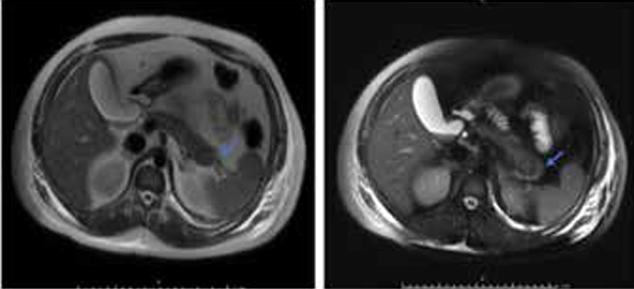

tecedente de déficit cognitivo leve y cuadro clínico de 4 años de evolución aproximadamente consistente en episodios convulsivos que curiosamente mitigaban con administración de “panela” molida, es valorado por neurología quien decide inicio de anticonvulsivante con levetiracetam. Es ingresado al servicio de urgencias en primer nivel por presentar deterioro progresivo del estado de consciencia, diaforesis difusa, palidez mucocutánea generalizada hasta episodios convulsivos tónicoclónicos generalizados sin recuperación inter crisis y evidencia de glucometría capilar de 25 mg/dl, por lo que se administran bolos continuos de dextrosa al 10% y benzodiacepinas. Posteriormente presenta deterioro del patrón respiratorio por lo que se procede a proteger la vía aérea con intubación orotraqueal (IOT) y se remite a tercer nivel de complejidad donde se inicia dextrosa al 50% por acceso central a razón de 7 a 10 gramos/hora con mejoría parcial del estado mental. Se solicitó radiografía de tórax con evidencia de neumonía broncoaspirativa con compromiso multilobar en hemitórax derecho por lo que se inicia cubrimiento antibiótico. Fue valorado por el servicio de medicina interna y endocrinología, quienes determinaron hipoglicemia en paciente no diabético con clínica compatible con triada de Whipple por lo que se consideró hiperinsulinismo endógeno, como primera posibilidad diagnostica insulinoma por lo que se iniciaron estudios de extensión donde se encontraron niveles elevados de insulina y péptido C (Tabla 1), además de resonancia nuclear magnética (RNM) de abdomen con evidencia de lesión focal de aproximadamente 27 x 24 mm en la cola del páncreas (Figura 1).

Figura 1: Resonancia nuclear magnética de abdomen. Lesión focal en la cola pancreática por sus características pudiendo corresponder a lesión de origen neuroendocrino.